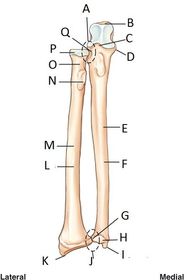

A. proximal radioulnar joint B. olecranon process C. coronoid process D. coronoid tubercle E. body/shaft F. ulna G. ulnar notch H. head I. styloid process J. distal radioulnar joint K. styloid process L. radius M. body/shaft N. radial tuberosity O. neck P. head Q. radial notch (on ulna)